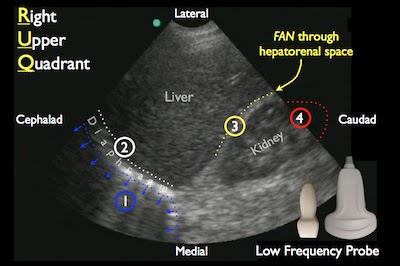

- Component: FAST abdominal views

- Probe: Phased array probe (3.5 – 5 MHz)

- Location: Hepatorenal recess, Splenorenal recess, and bladder

- Finding: Internal blood loss